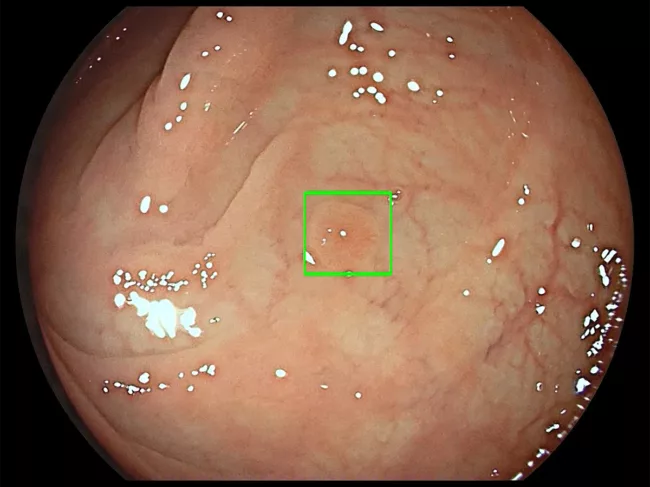

Image from GI Genius intelligent endoscopy module

Medtronic’s GI Genius in study for detecting adenomas during colonoscopy

A 2,000-patient U.K. study has been set up to generate real-world evidence of the value of using AI technology to detect bowel polyps (adenomas) during colonoscopy procedures. The aim is to show whether Medtronic plc’s GI Genius system improves the detection of polyps when deployed in both expert centers and non-specialist units, in the routine diagnostic screening of patients referred from primary care or through the national fecal immunochemical testing program. Read More